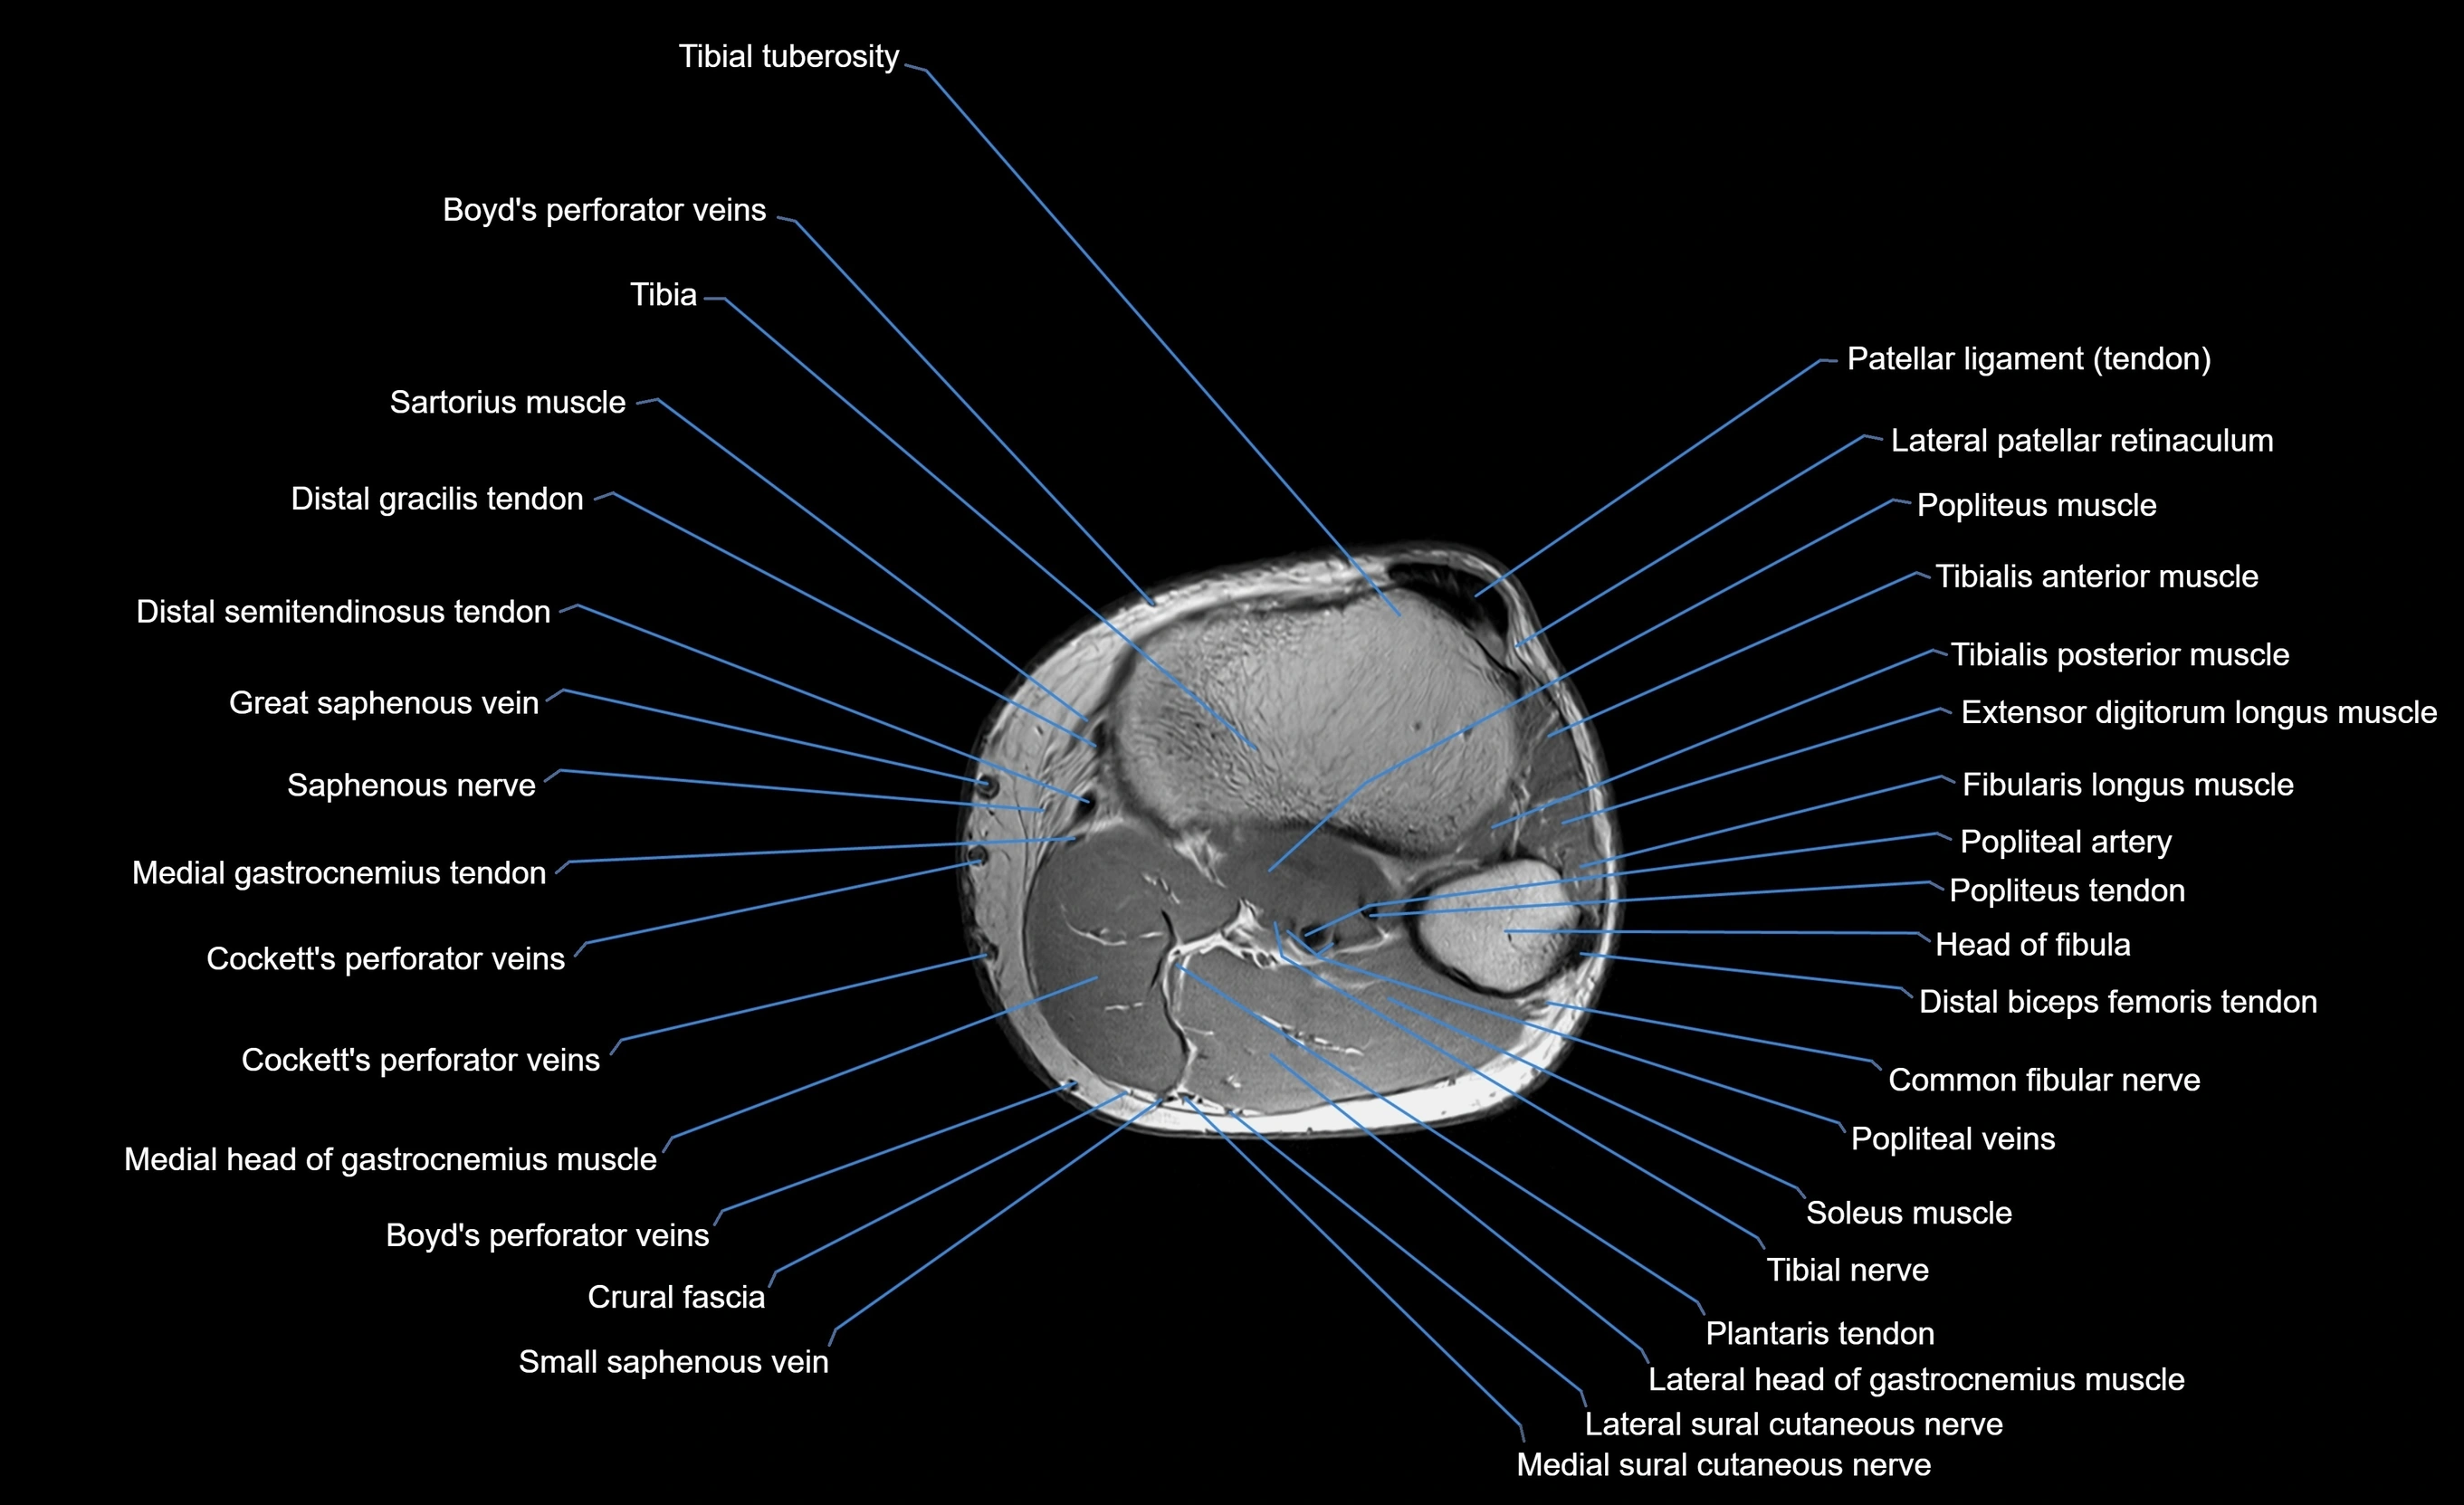

MRI image